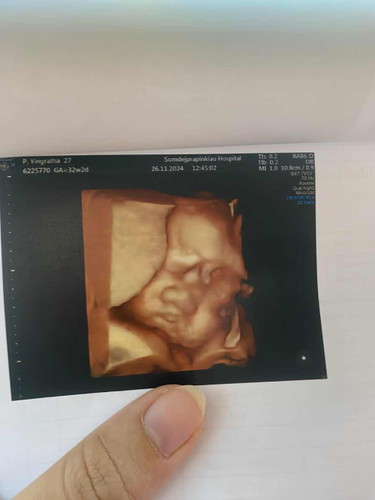

32สัปดาห์2วัน

น้ำหนักน้อง2561g แม่ๆบ้านไหนให้เยอะกว่านี้ไหมค่ะ มาแชร์กันได้จ้า อาจารย์หมอเอ็นดูแก้มน้องมาก🥰🥰